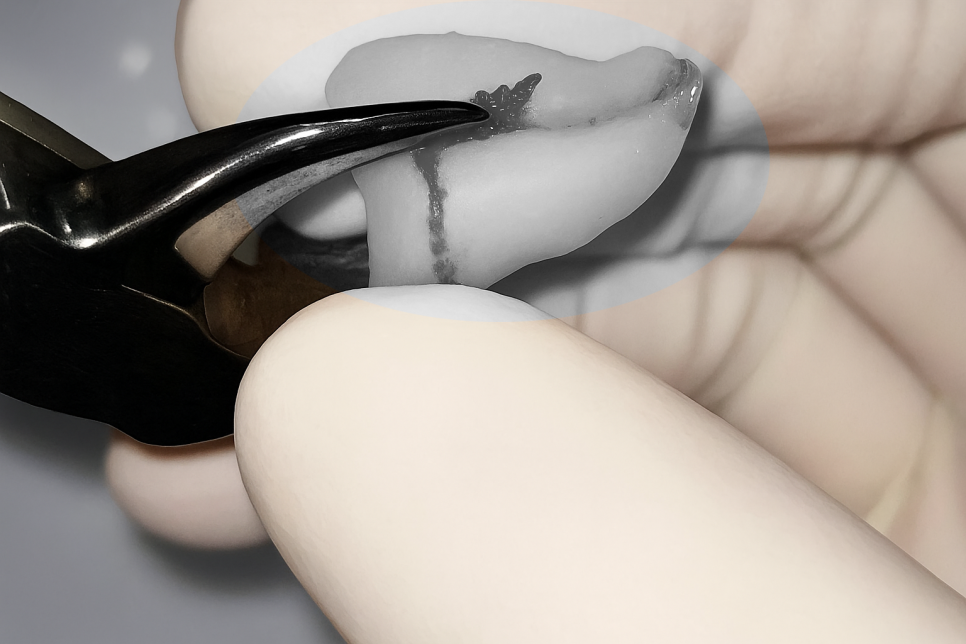

치아를 손으로 쥐고 있는 모습을 보시면

아주 작은 것을 알 수 있습니다.

그 안에는 매우 여러 요소들이 있죠.

신경치료 단계에서는 작은 통로를 형성하여

작은 내부 구조를 제거하고 소독하여

청결을 도모하는 단계를 거쳐야 된답니다.

그래서 비교적 까다롭고 섬세한 작업이 필요한데,

이 과정에서 도움을 주는 것이 미세현미경이랍니다.